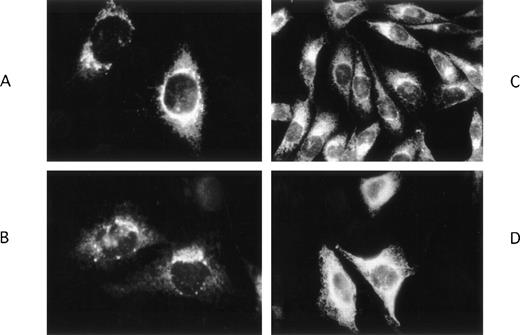

Using immunohistochemical techniques to detect intracellular VII:Ag, we found different patterns of localization for FVIIwt, FVIICys97, and FVIIArg100. Staining of FVIIwt (Fig 2A and B) and FVIICys97 (Fig 2C) was mostly perinuclear suggesting that these molecules were localized primarily in the Golgi apparatus. In contrast, FVIIArg100 (Fig 2D) staining was predominantly diffuse without perinuclear enhancement, suggesting that it was retained for a longer duration of time in the endoplasmic reticulum (ER) than the other recombinant proteins.

Immunohistochemical localization of wild-type and mutant FVII molecules in stably transfected CHO cells. FVIIwt (A, B) and FVIICys 97 (C) were mostly localized in the perinuclear area, whereas FVIIArg100 (D) was present diffusely throughout the cytoplasm without perinuclear enhancement. Untransfected CHO cells did not react with either the anti-FVII Mab or the fluorescent second antibody indicating that the observed labeling was specific for FVII (data not shown).